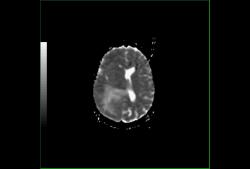

Диффузионно-взвешенные